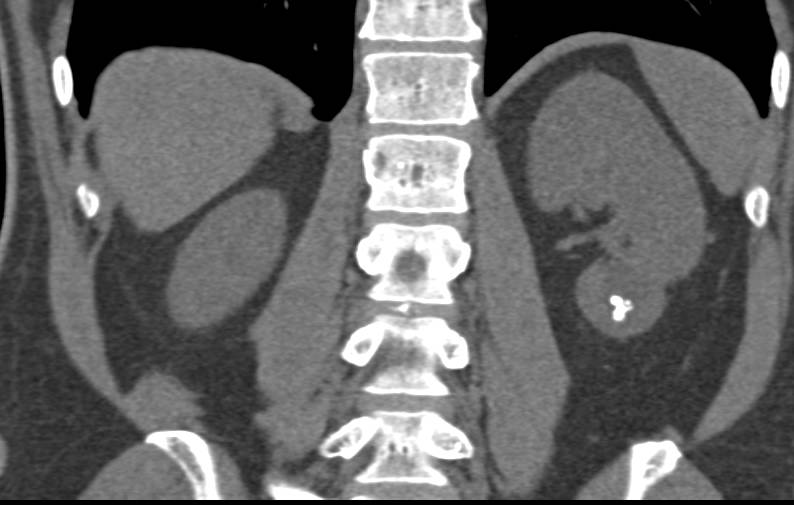

Multiple Left Renal Arteries Nicely Defined in a Potential Renal Donor